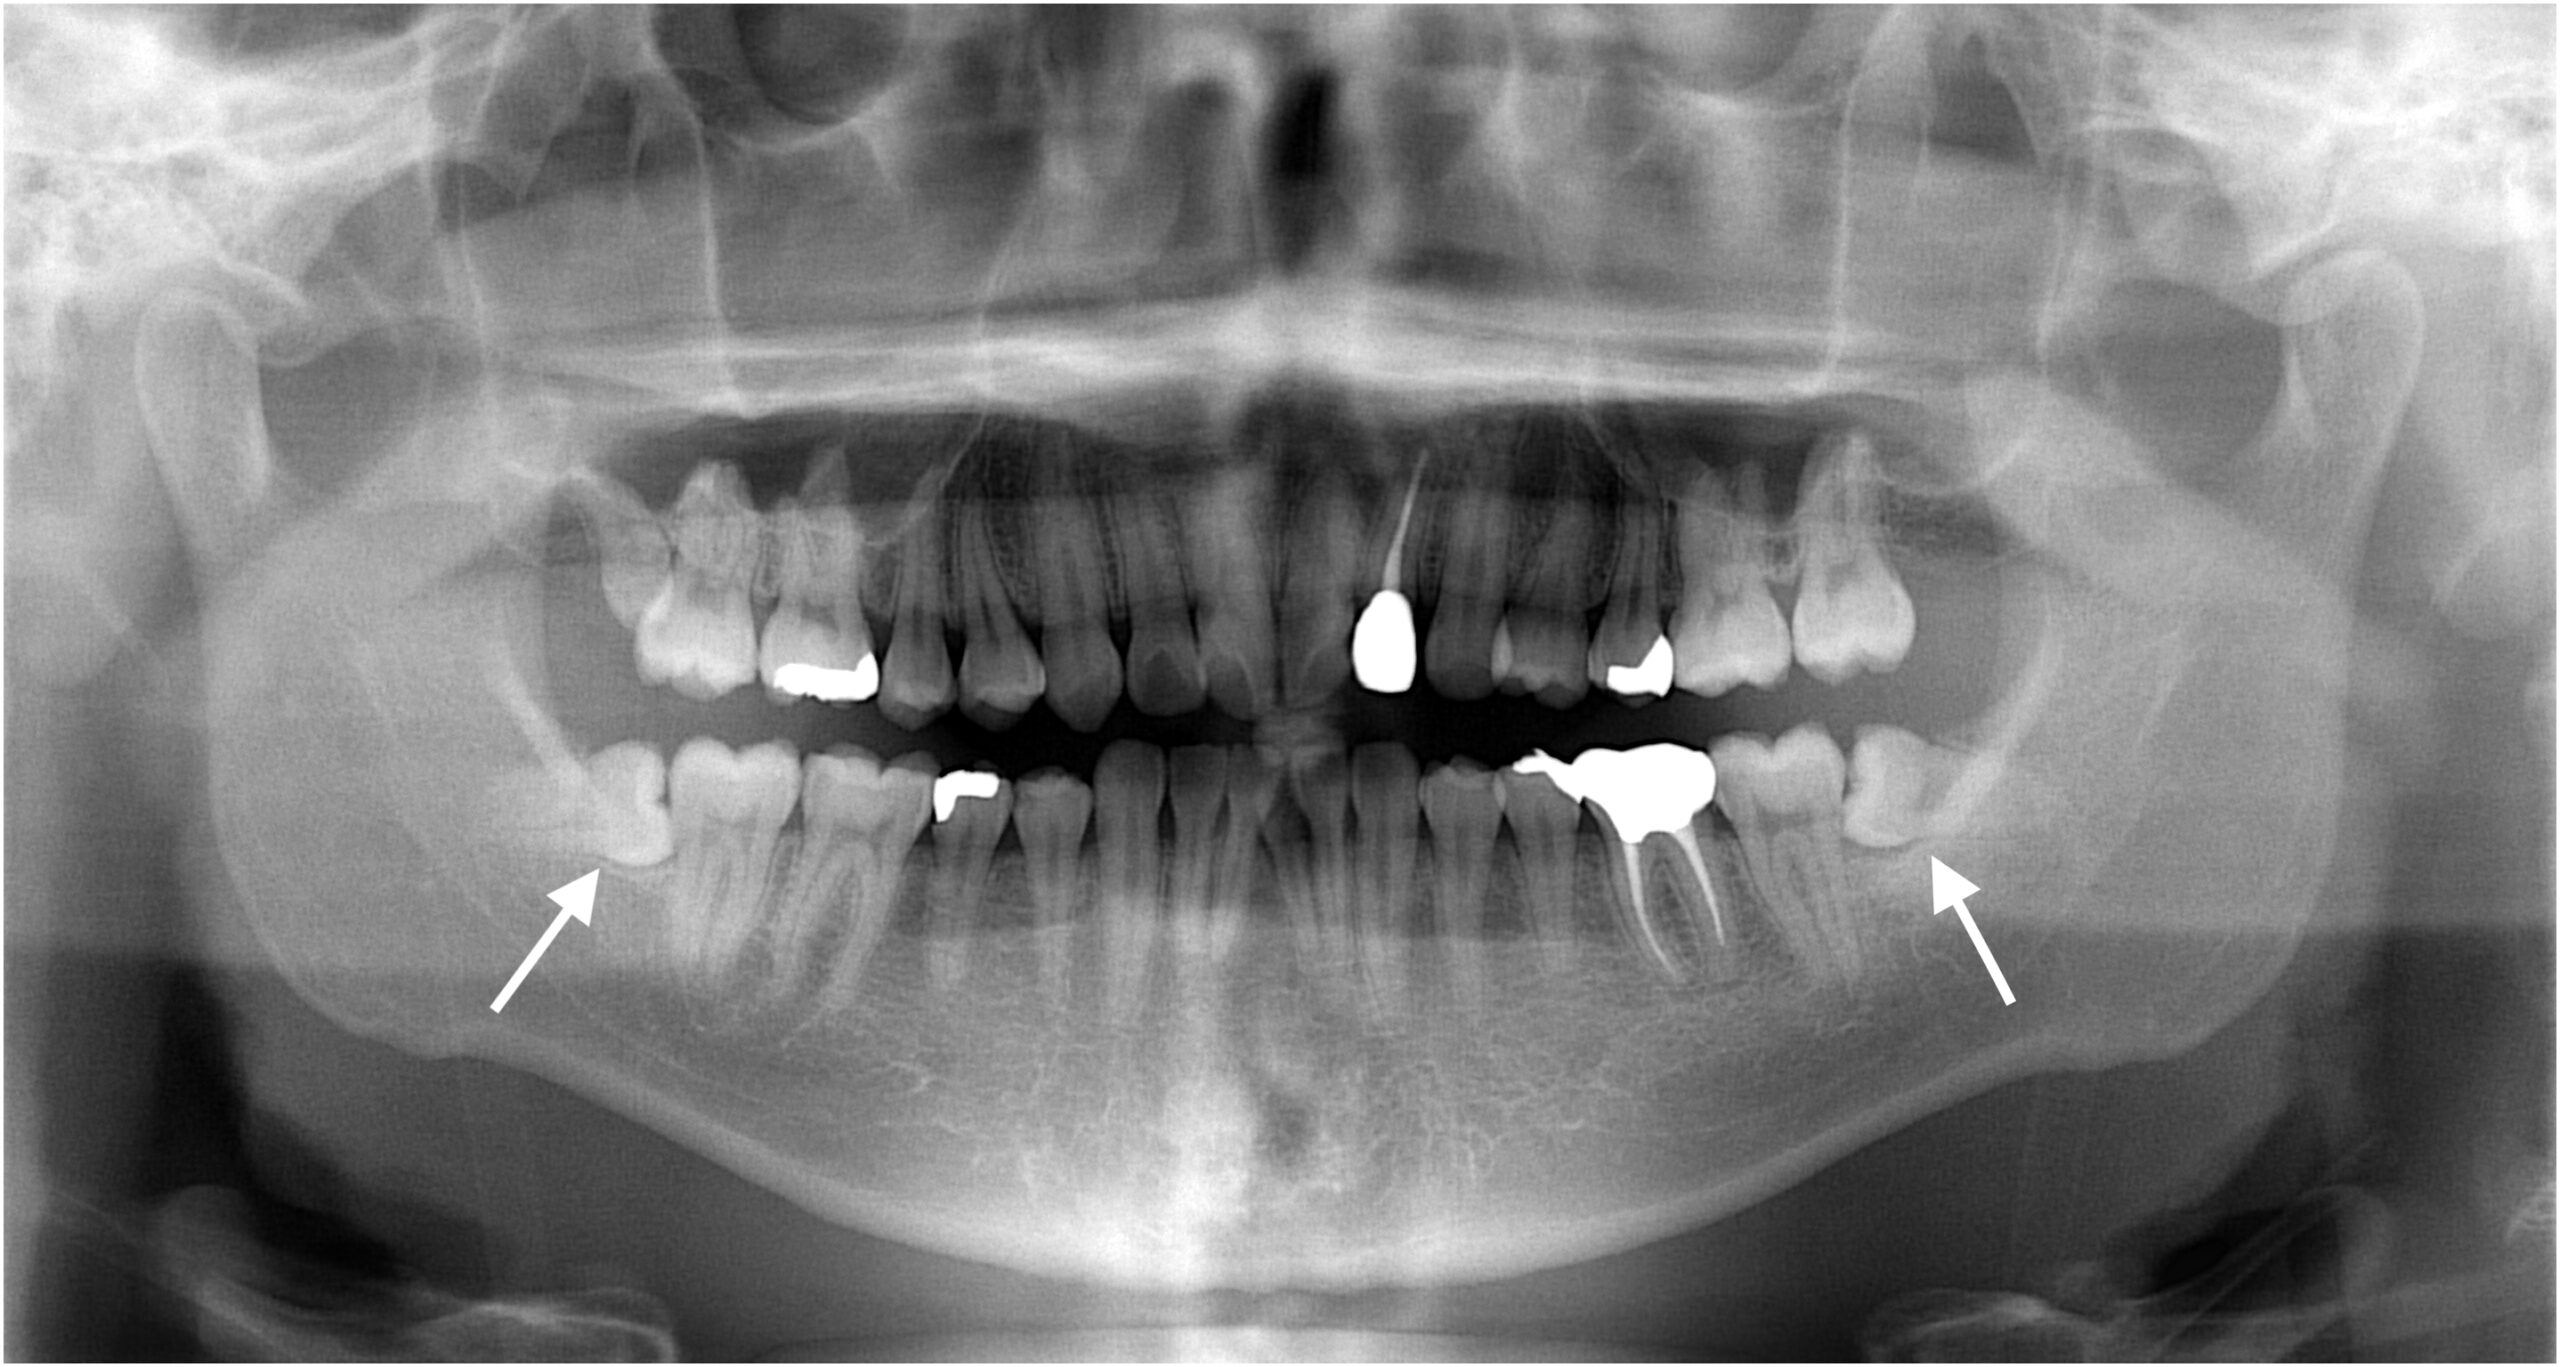

などの場合は、将来のトラブル予防のために抜歯を検討します。抜歯の難易度は「生え方」「根の形」「神経との距離」などで変わるため、まずは診査・画像検査で安全性を確認します。